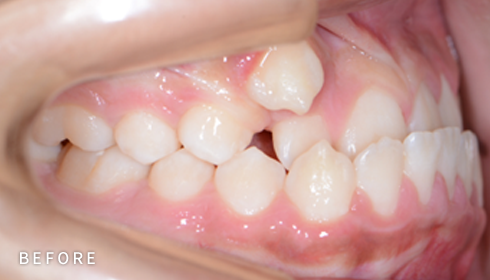

비발치 덧니 교정

덧니고민, 비발치로 교정하세요

악궁 확장, 미니 스크류, 치간 삭제 등 다양한 방법을 활용해 가능한 한

발치를 피하고, 자연스럽고 만족스러운 결과를 얻을 수 있도록

정밀하게 계획하고 진료합니다. 발치 여부가 애매한 경우,

‘레벨링 후 재평가’ 과정을 거쳐 비발치를 우선 고려합니다.